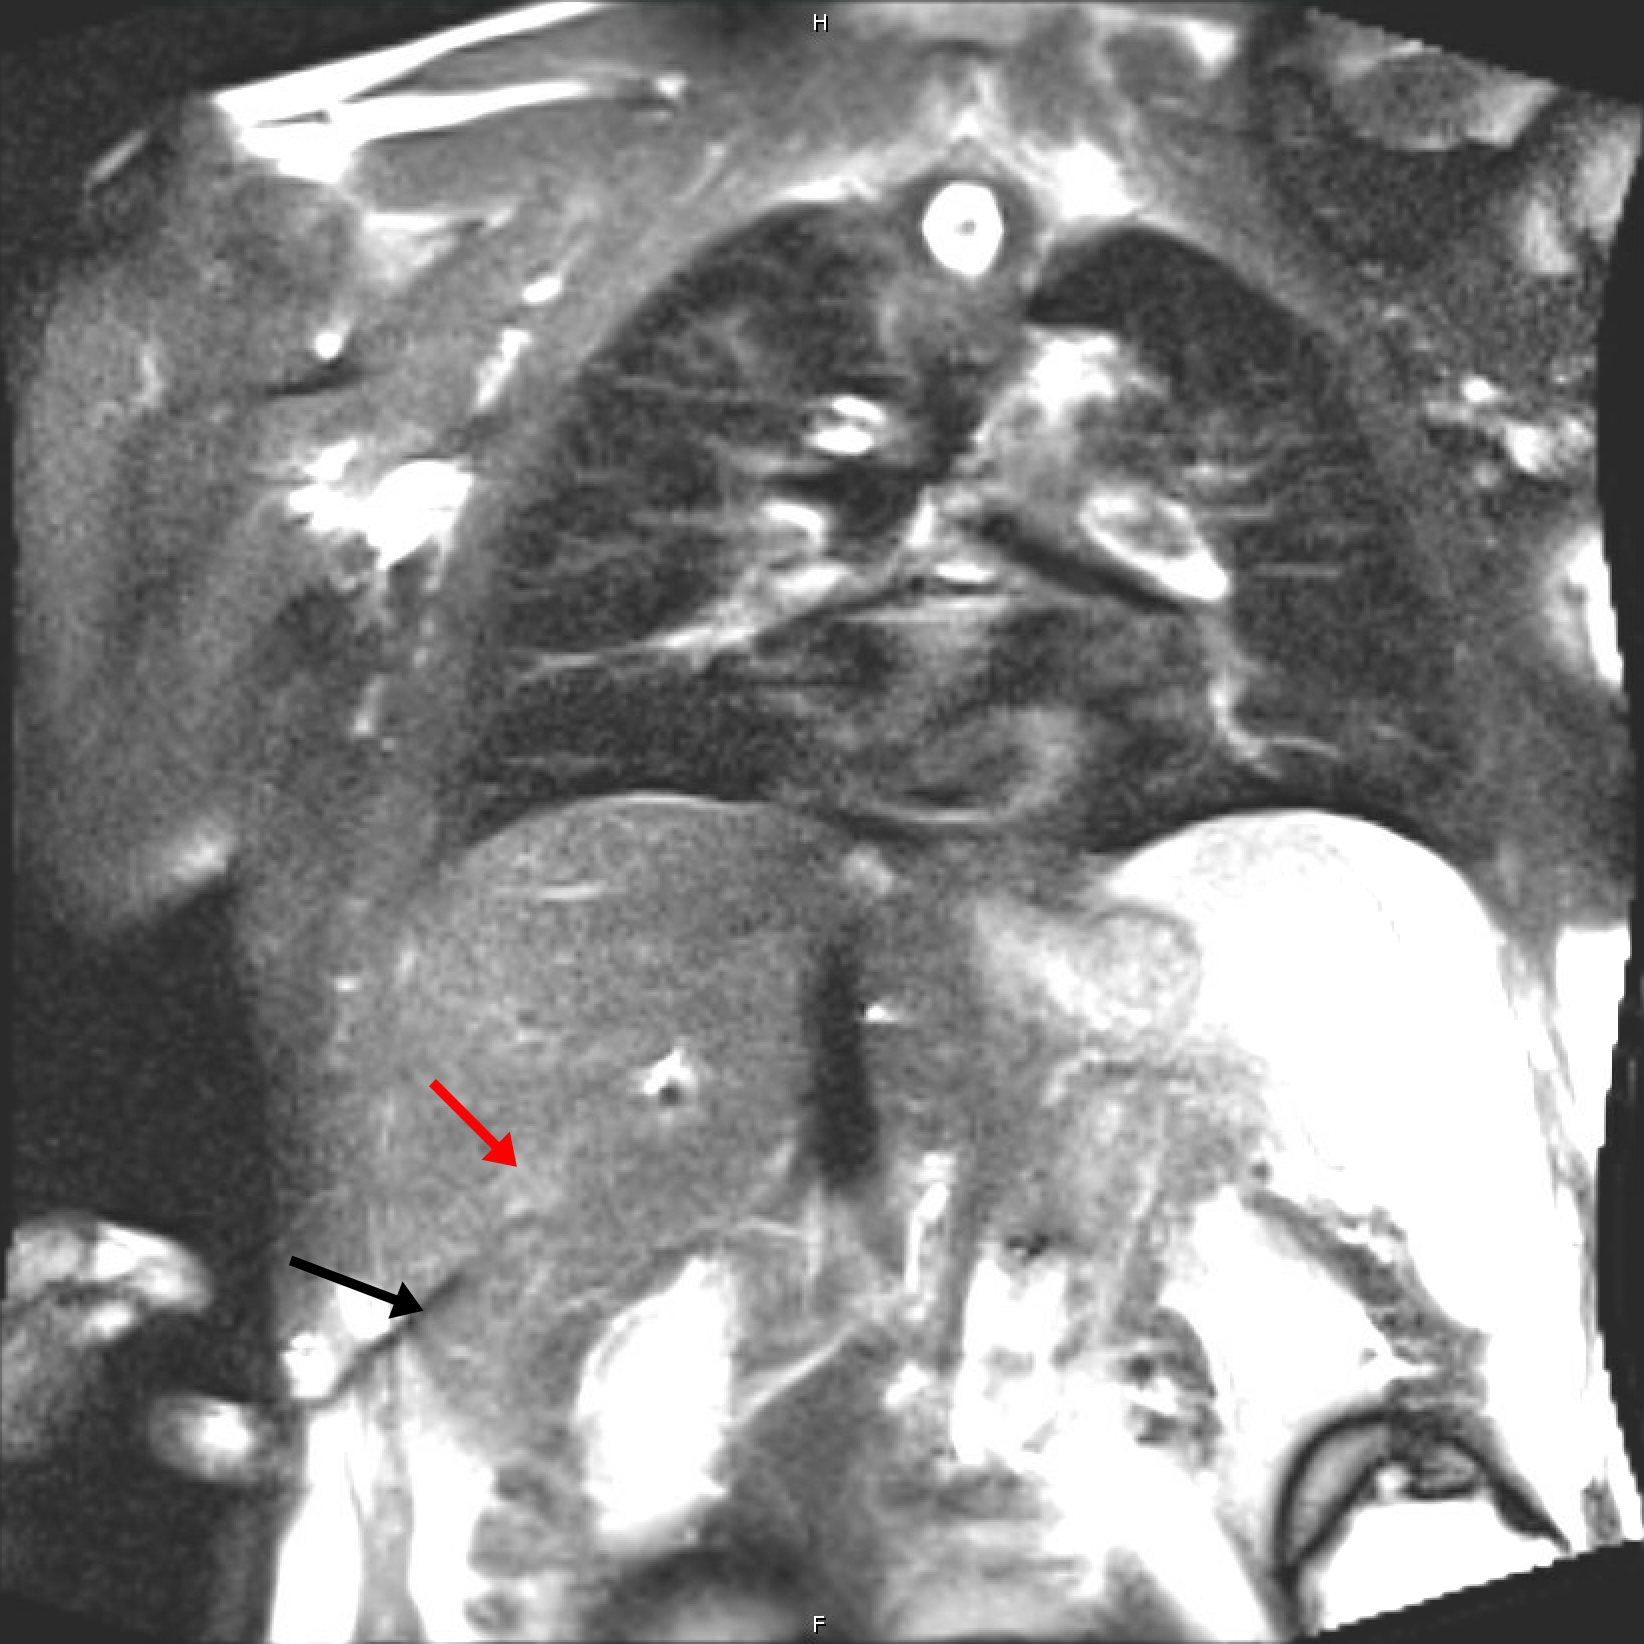

MR-guided biopsy is a minimally invasive medical procedure that utilizes magnetic resonance imaging (MRI) technology to guide the precise sampling of tissue from within the body. This advanced technique is commonly employed in the diagnosis and assessment of various medical conditions, particularly in the detection of suspicious or hard-to-reach lesions, tumors, or abnormalities. MR-guided biopsies offer the advantage of including real-time visualization of the target area. This approach is especially valuable in oncology, as it aids in obtaining representative tissue samples for accurate diagnosis and treatment planning, ultimately contributing to better patient care and outcomes. Below you can see a typical case for a MR-guided biopsy on the liver where the needle is inserted into the tumor tissue (Fig. 5).